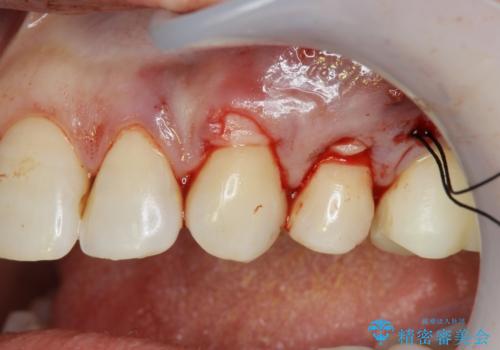

改善を図るため、結合組織移植を行い歯ぐきの再生を計画します。

手術を行い歯ぐきの位置が改善することで歯がしみる症状が大幅に改善されたと満足いただくことができました。

- 外科手術のため、術後に出血、痛みや腫れ、違和感を伴います

- 口腔内の状態によっては適応できないことがあります